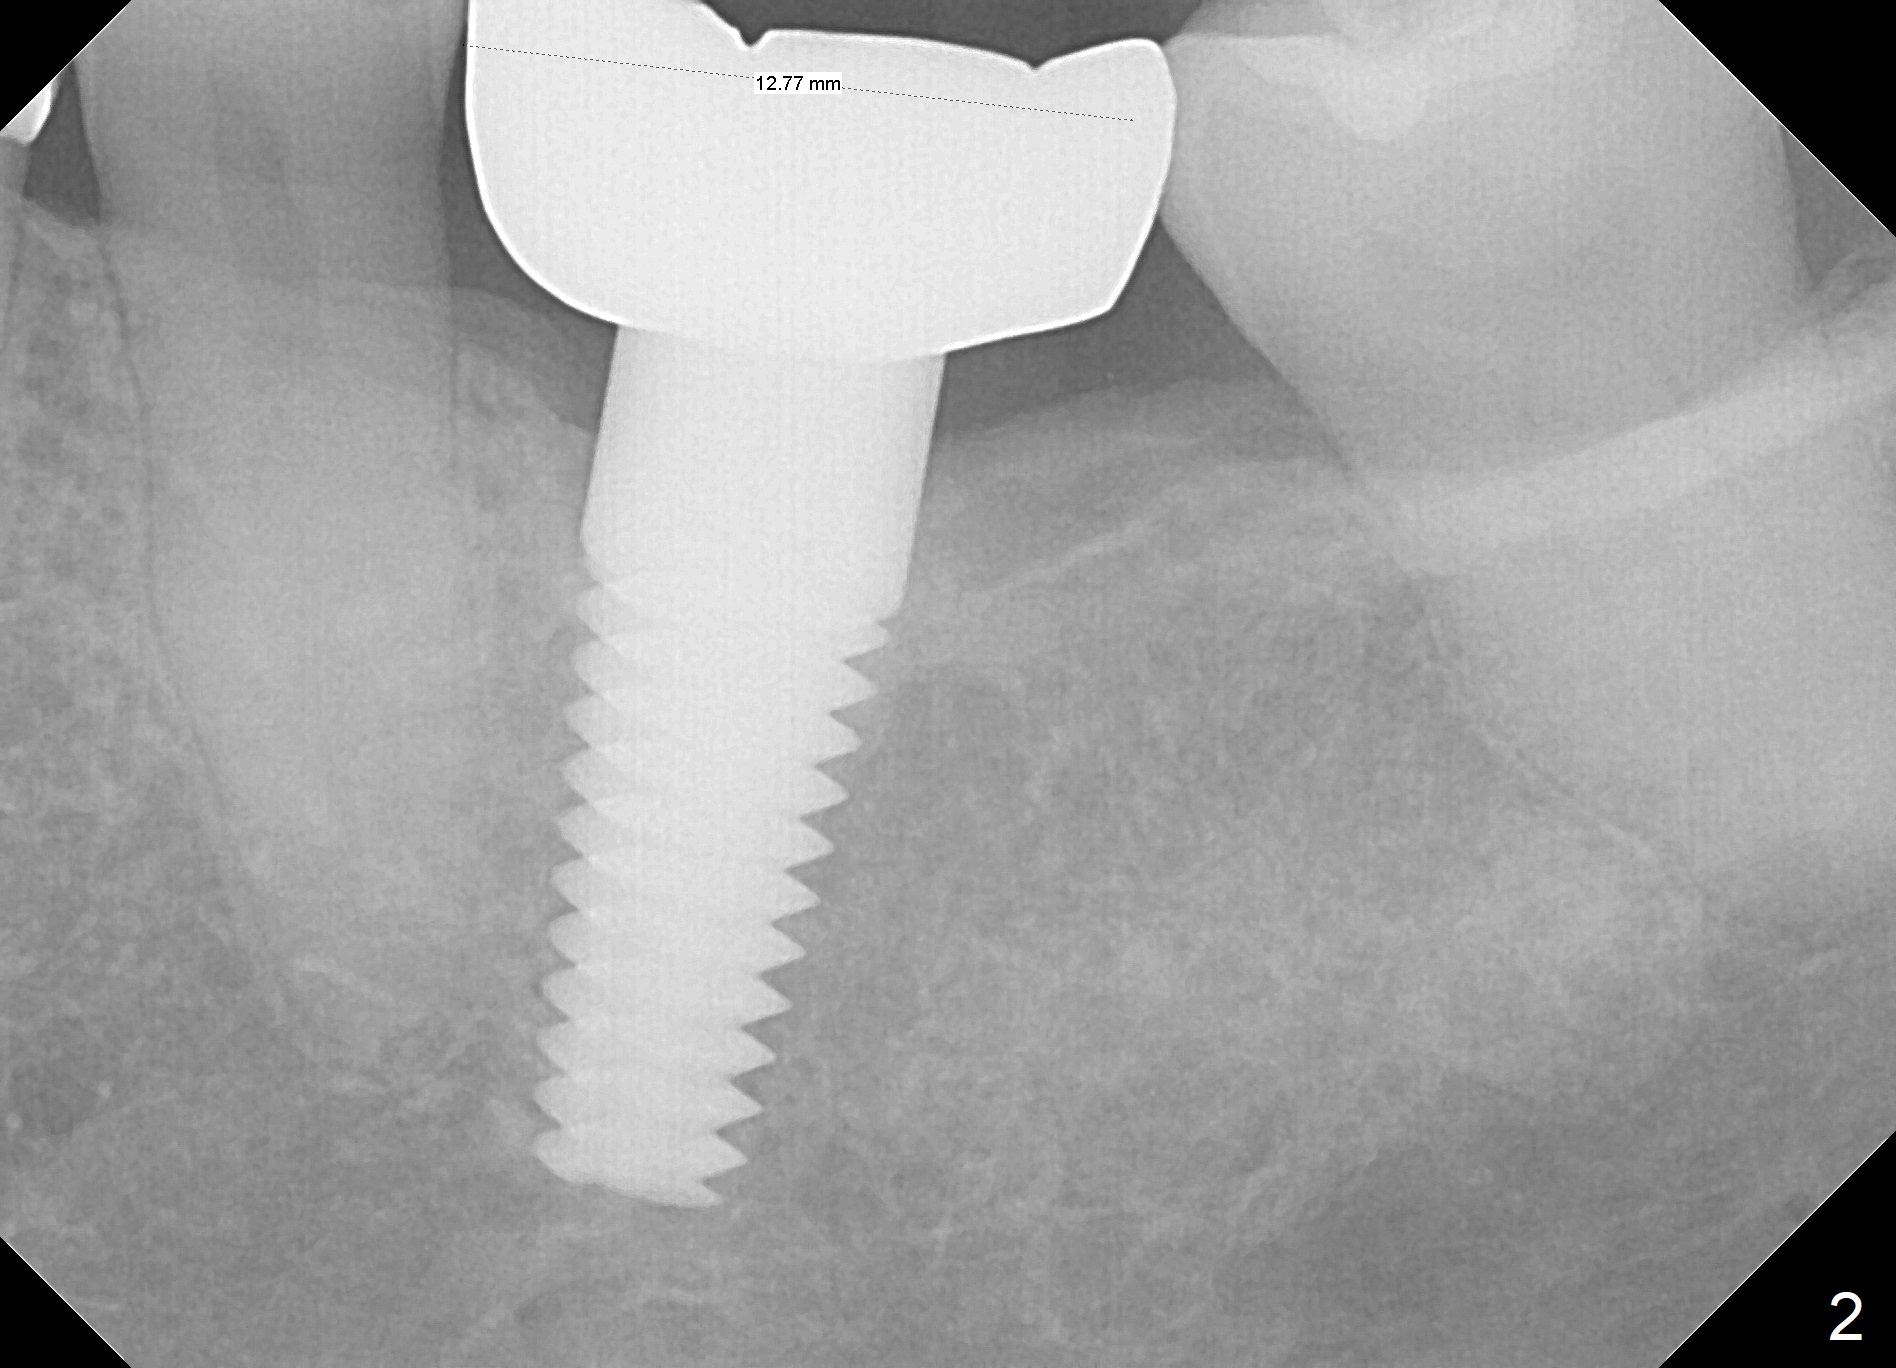

A 53-year-old woman returns for follow-up, requesting implant restoration at the sites of #30 and 31.  The edentulous space is ~14 mm mesiodistally (Fig.1), whereas a 6x17 mm implant was placed at #19 with ~13 mm space (Fig.2).  If the ridge at the LR molar region is wide enough buccolingually (3.5-5 mm Implant Positioners), place one implant (Fig.3, 4 mm Implant Spacer).  Otherwise, two of them will be placed (Fig.4).